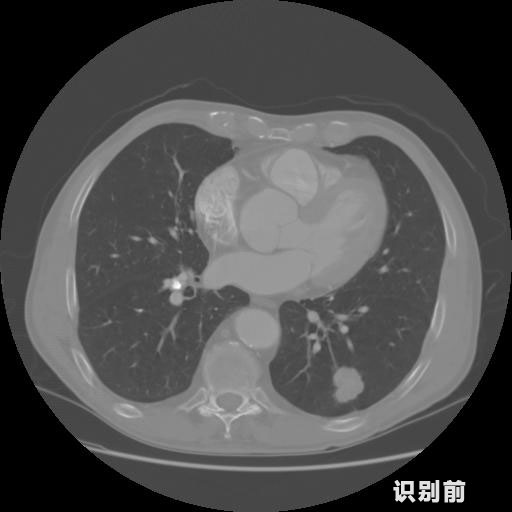

1.發(fā)現(xiàn)肺結(jié)節(jié)的可能性為95.56%---位于框指數(shù)位置:[331.70554 366.13406 365.21707 403.96234]